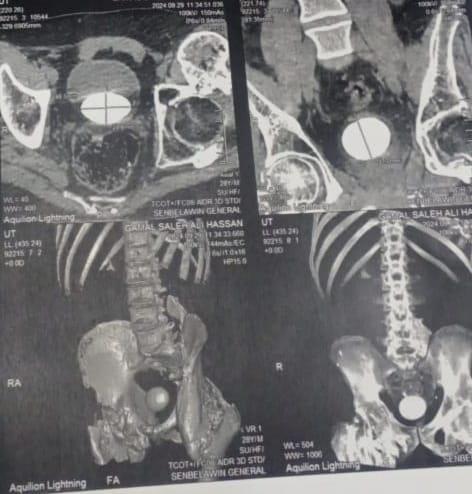

شهد مستشفى كفر صقر المركزي بمحافظة الشرقية، إجراء عملية جراحية بوحدة تفتيت الحصوات الكلوية ومناظير والمسالك البولية الفريدة لشاب في أواخر العشرينات باستخراج حصوة حجمها 8 سم مم الحالب وكان يعاني ظروفا صحية خاصة.

ولفت مدير المستشفى، إلى إجراء عملية استخراج حصوة من الحالب بحجم 8 سم لشاب عشريني يعاني ظروف صحية خاصة كان تعرض لحادث منذ عدة سنوات تسبب له في نزيف بالمخ أدى إلى ضمور المخ وفقد التحكم والحركة للنصف السفلي، بالإضافة إلى فقدان النطق وأعراض جانبية أخرى.

وبعد إجراء العملية بنجاح للمريض، جري تركيب دعامات للحالة فضلا عن إجراء تفتيت حصوات كلوية للمرضى بالقسم وحالات منظار مسالك بولية مع عمل القسم على أكمل وجه واستقبال الحالات يوميا.